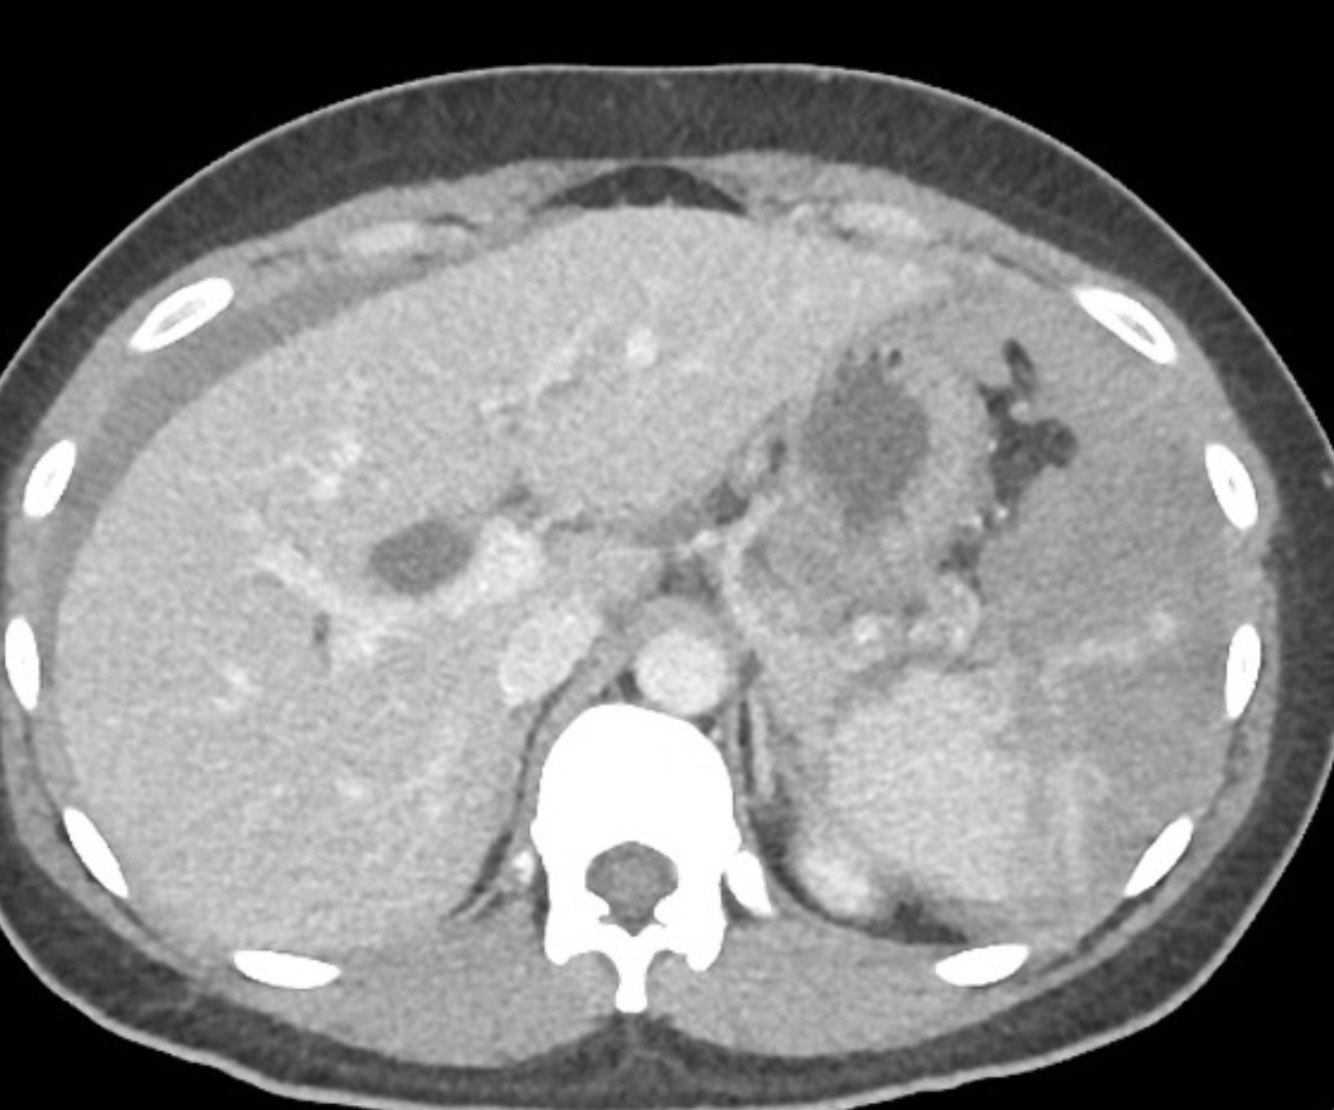

what nuc med scan can be used to diagnose this condition?

Splenosis is one type of ectopic splenic tissue (the other being accessory spleen). It is an acquired condition and is defined as autoimplantation of one or more focal deposits of splenic tissue in various compartments of the body.

Abdominal splenosis is seen after abdominal trauma or surgery (e.g. splenectomy). It results from seeding of the peritoneal cavity with splenic tissue which recruits local blood supply. The ectopic splenic foci are typically small, sessile (as they grow on serosal/peritoneal surfaces) and multiple. They may grow over time to become quite sizeable. If located only intrahepatically, they can cause serious diagnostic problems.

CT

They are typically rounded or sessile nodules, and have density and enhancing characteristics similar to the rest of the spleen, or expected density of the spleen if there has been a splenectomy.

Tc-99m-tagged heat-damaged RBC scan (Tc-99m-DRBC) with autologous erythrocytes shows accumulation in the abdominal cavity, consistent with intra-abdominal splenosis.

Case Discussion

Main concern for intra-abdominal lesions found on CT scan was for metastatic disease. Using heat treated RBC confirmed the functioning splenosis at the various abdominal sites.